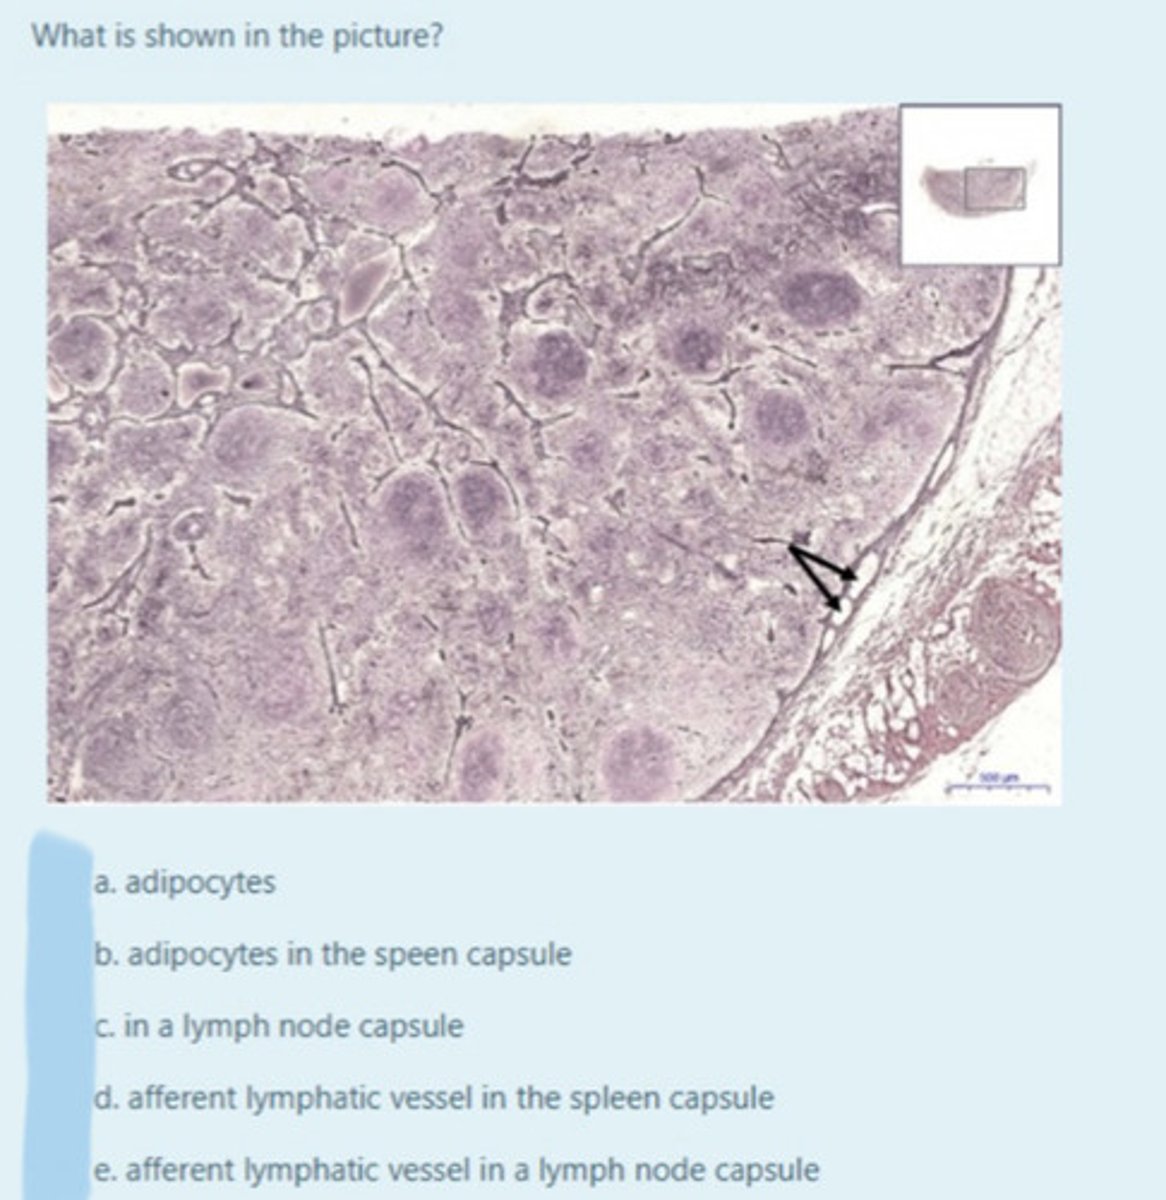

What makes up the adult thymus?

It contains 𝐚𝐛𝐮𝐧𝐝𝐚𝐧𝐭 𝐚𝐝𝐢𝐩𝐨𝐜𝐲𝐭𝐞𝐬 (fat cells in the subcutaneous layer in the thymus) and 𝐟𝐢𝐛𝐫𝐨𝐮𝐬 𝐜𝐨𝐧𝐧𝐞𝐜𝐭𝐢𝐯𝐞 𝐭𝐢𝐬𝐬𝐮𝐞 (tissue that forms the thymic capsule)